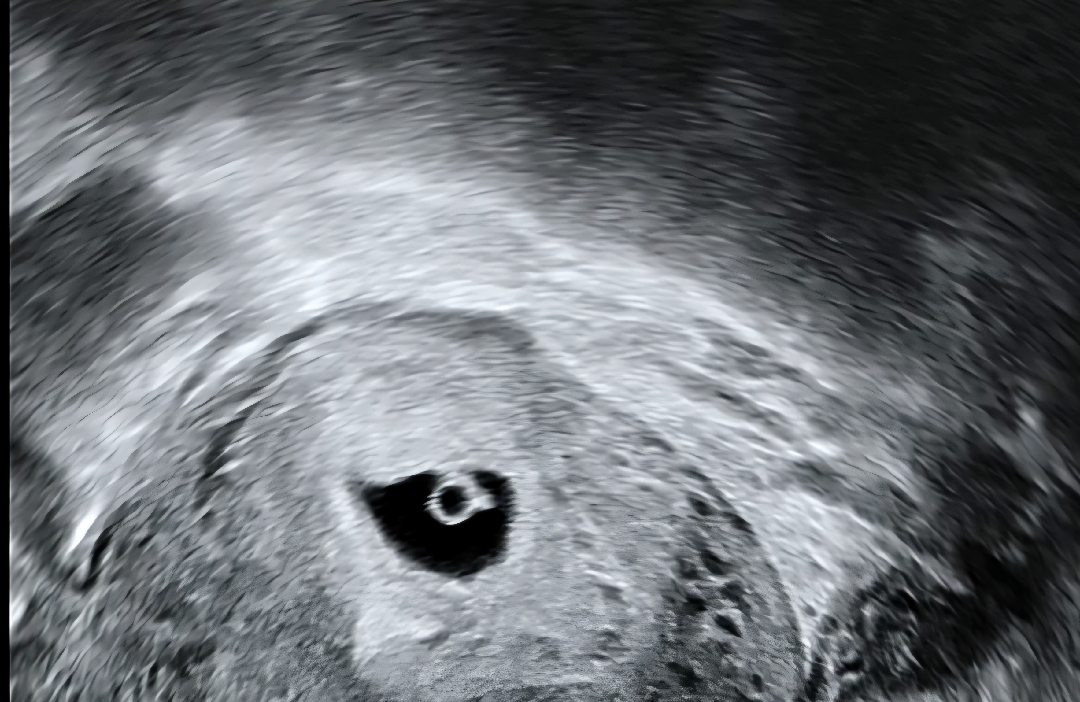

네이버 주수로는 6주 1일 나오는데 아기 크기는 5~6주 사이 같다고 하시더라고요! 대략적으로 잡아주신 출산예정일로 따지만 5주 4일 정도 됐어요. 6월 23일에 진료 갔을 때는 아주 희미한 난황보여주더니 오늘은 5일만에 난황도 또렷하게 보이고 작게 자라 있었어요 ㅎㅎ 이쁜 다이아몬드 반지도 보고 선생님이 아기가 작아서 들릴 지는 모르겠지만 한번 들어볼게요 하는 순간 심장 깜빡임이랑 심장소리 들리더라고요 2주 뒤에 검진 오라고 하시는 데 시간이 또 안 갈 것 같아요 ㅠㅠ